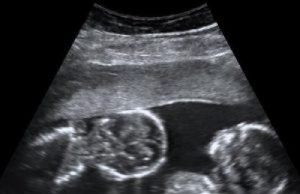

Twins and Breech Babies: Human Birth, Part 4

In this comprehensive series of normal labor and delivery off the grid, we’ve discussed late-term pregnancy, the signs of impending labor, the progress through...